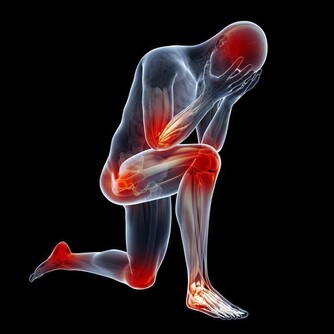

頸椎病本是中老年人的常見疾病,可是隨著年輕人的工作習慣等問題,不少人年紀輕輕就開始遭受頸椎病痛的折磨,白天辛苦工作一天,晚上頸椎還痛的睡不著。頸椎病可導致頸肩痛、頭暈頭痛、四肢無力等,嚴重者甚至出現肌肉萎縮、下肢痙攣、大小便失禁、癱瘓等,治療頸椎病刻不容緩。